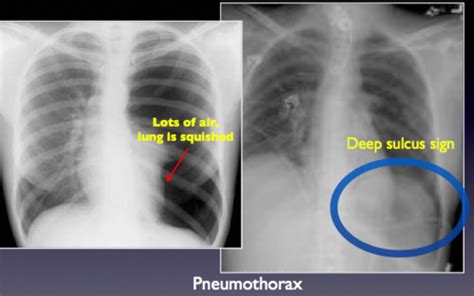

Deep sulcus sign - Wikipedia

en.wikipedia.org

RESP Blood exam Flashcards | Quizlet

How to pick a pneumothorax on a supine CXR - Emergency Medicine Kenya Foundation

DEEP LATERAL SULCUS SIGN - Radiology Classroom | Facebook